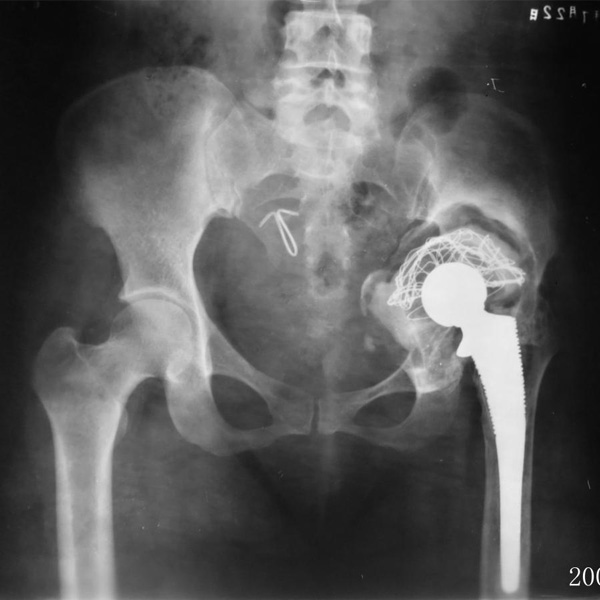

髖關節翻修

患者蘇某,女性,11年前因“左髖關節屈曲攣縮畸形”行左側人工全髖關節置換,近來感覺左髖關節疼痛,不敢行走,經“攜生醫療平臺”就診于哈......